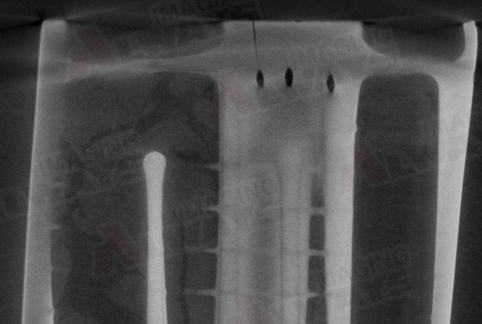

●孔洞:是指物体内部存在的空隙或空洞,如气孔、脱碳层等。孔洞会降低物体的密度、强度、刚度等。

识别X射线工业CT图像中的缺陷,主要是通过观察和分析CT图像的像素值、灰度、对比度、形状、位置等特征,判断是否存在缺陷,以及缺陷的类型、大小、数量、分布等。一般来说,缺陷的识别方法可以分为以下两种:

●主观识别:是指人工观察和判断CT图像,根据经验和直觉,识别出缺陷的存在和特征。这种方法简单易行,但是受到人的主观因素、视觉疲劳、判断标准等的影响,容易出现误判或漏判。

●客观识别:是指利用计算机和图像处理软件,根据一定的算法和规则,自动或半自动地识别CT图像中的缺陷。这种方法准确可靠,但是需要较高的计算能力和图像质量,以及合理的参数设置和阈值选择。